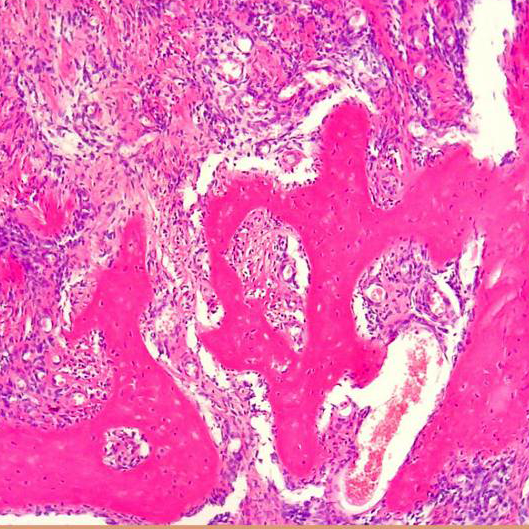

Se recibe pieza de nodulectomía. A la inspección macroscópica era un nódulo sólido bien circunscripto, blanquecino con áreas quísticas y hemorrágicas.